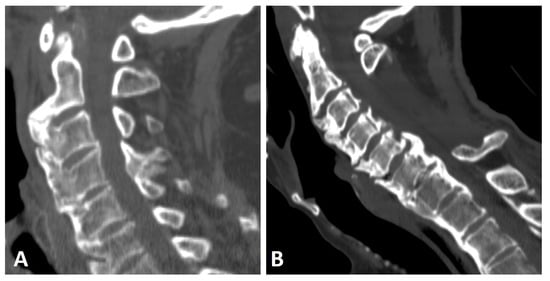

Anterior ossification of the spine in DISH may involve the cervical spine, primarily along the lower half of the anterior border of the vertebral body, forming a “candle flame” or “parrot-beak” image (Figure 2) [32]. These cervical flowing osteophytes are frequently asymptomatic but may result in dysphagia, sleep apnea, airway obstruction, and difficulty in intubation [7,23,33]. It has been reported that approximately one-third (33%) of subjects with DISH involving the middle or lower thoracic region have coexisting DISH in the cervical spine, according to whole-spine computed tomography (CT) [34].

Figure 2.

Sagittal CT reconstruction images of two patients with thoracic (not shown) and cervical DISH. (A) Flowing chunky osteophytes are located anteriorly to the vertebrae, forming a “candle flame” or “parrot-beak” image. (B) Thick, not-yet-flowing anterior osteophytes and thick posterior osteophytes at the C5–6 level.